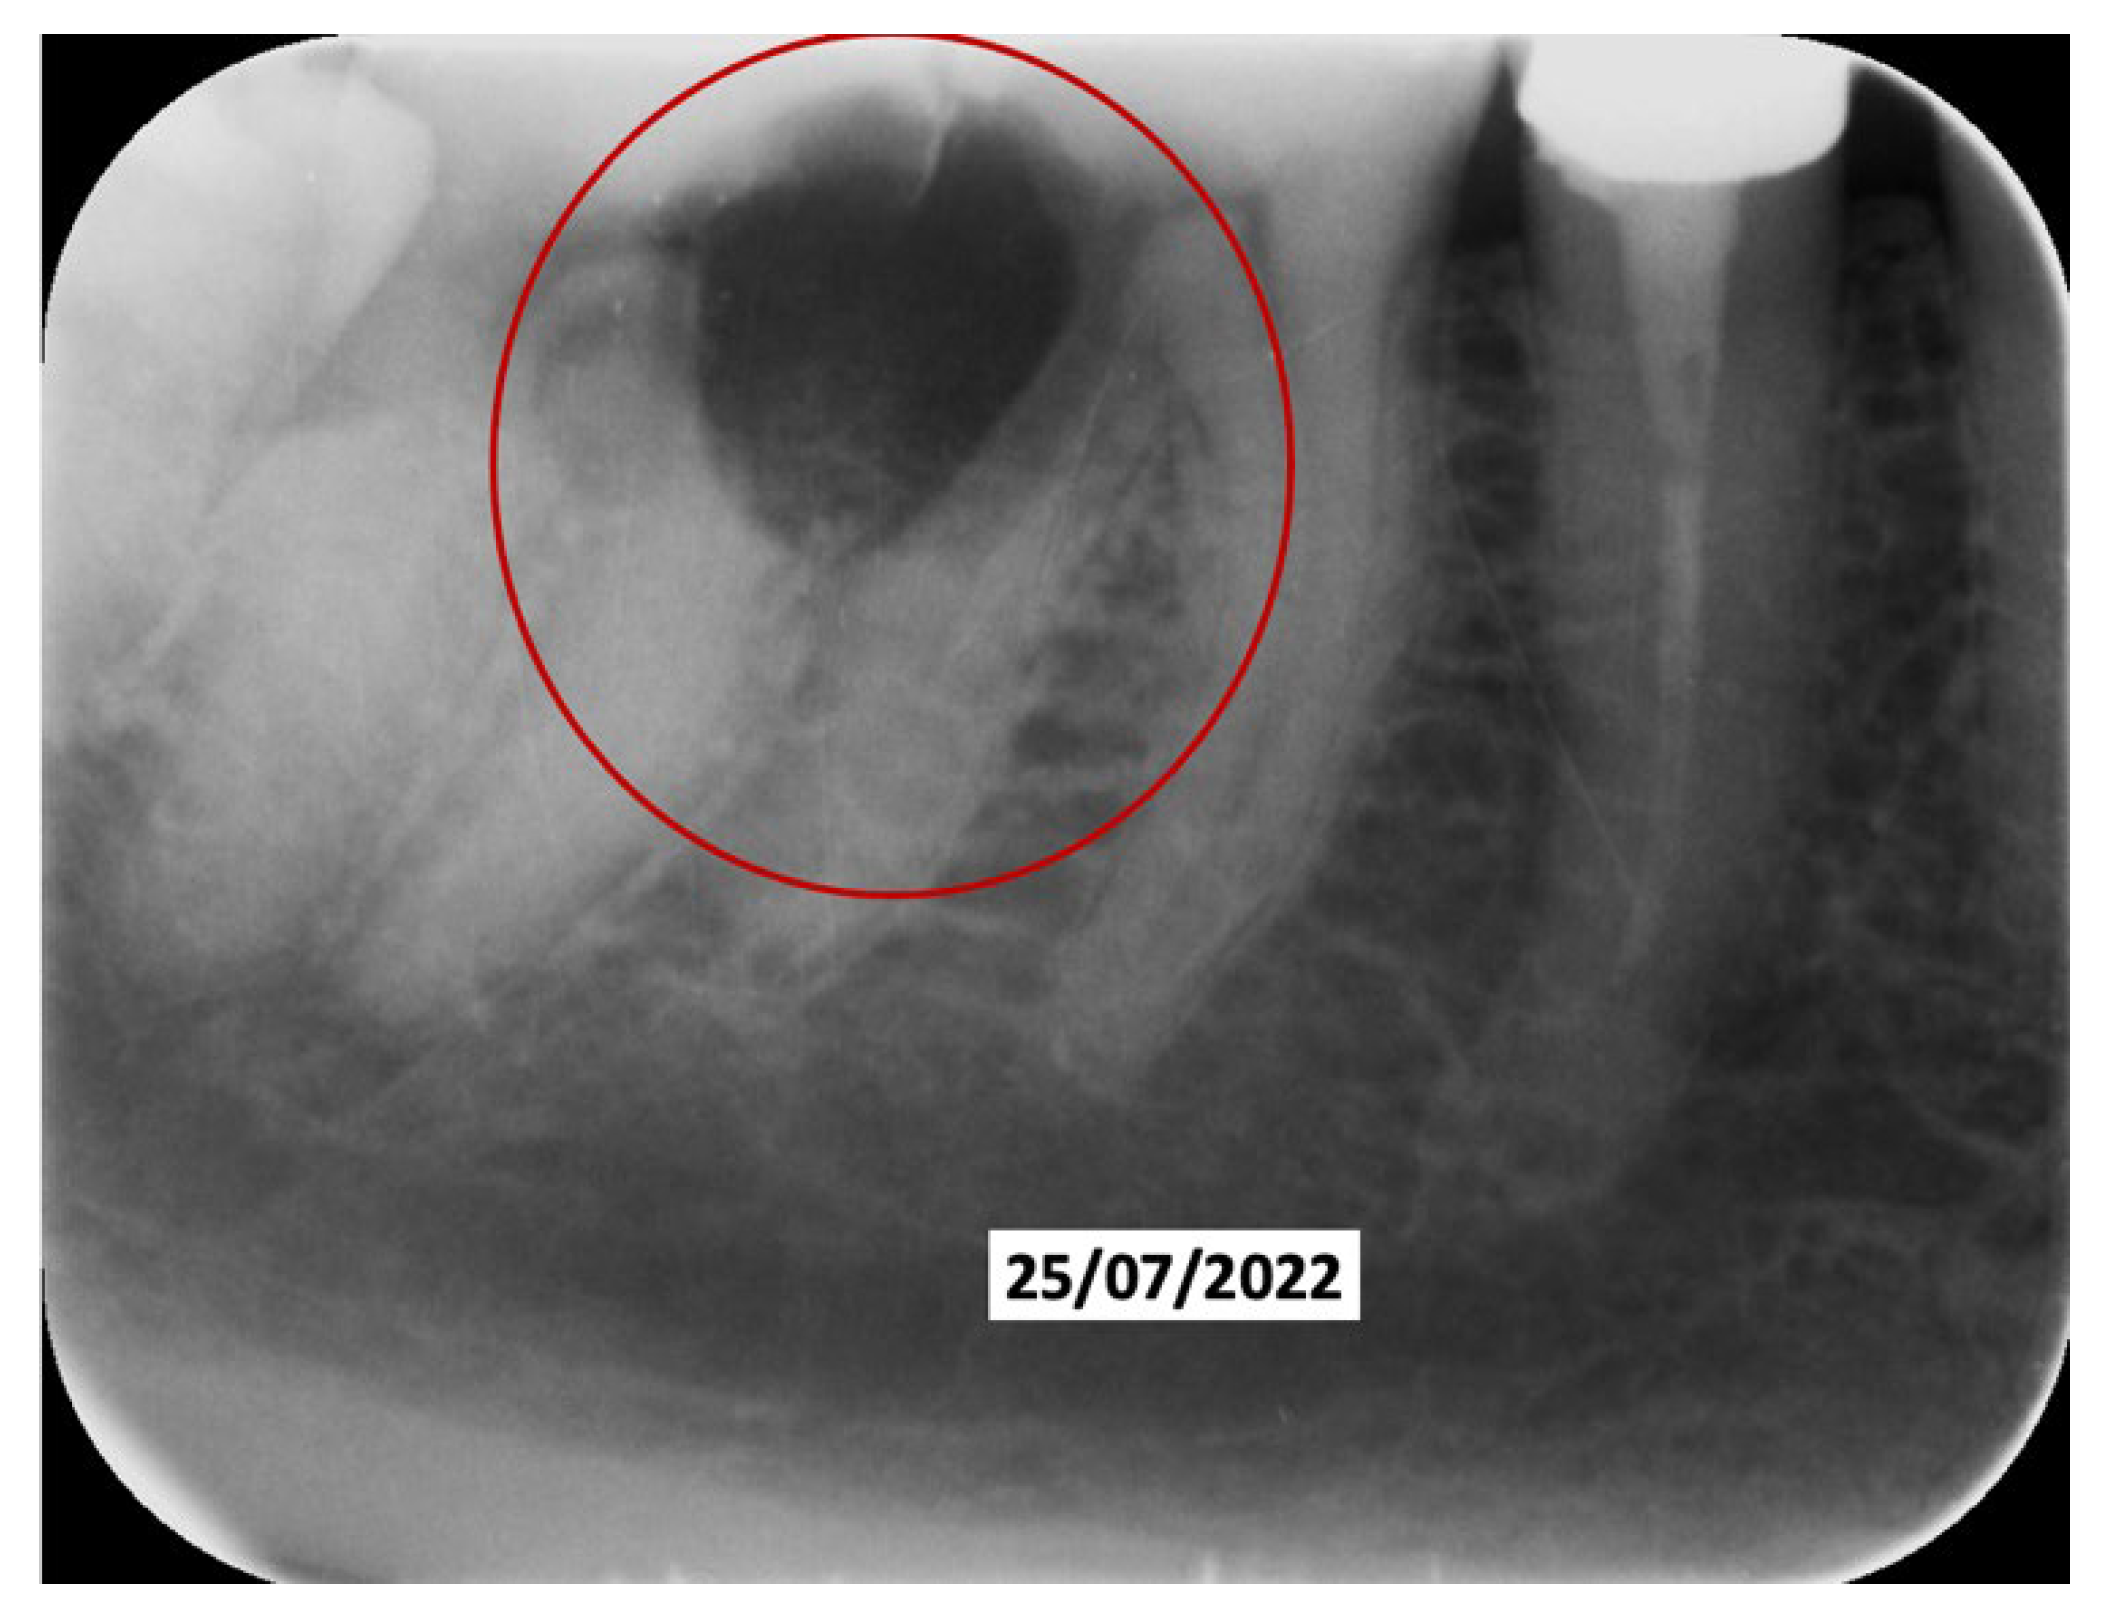

A 52-year-old patient, affected by non-Hodgkin lymphoma since March 2020 and treated with denosumab until June 2021, in clinical remission, presented in January 2022 for observation with multiple root resorptions, not of endodontic origin; it initially affected 22-21-11, but then, with rapid evolution, also affected 23-12-13-14-15-16-17-46-47, without referred pain. The resorption phenomena ended in September 2022. Since then, every radiographic check-up carried out to verify the progress of the regenerative bone surgeries has confirmed the arrest of the progression of the resorption phenomenon affecting the residual dental roots. In February 2022, as soon as responsibility for the patient’s care was assumed, in agreement with the oncology department of the hospital in Bergamo in which he was in care, given the severity of the lesions present (Figure 2), it was decided to extract the teeth (22-21-11), with a surgical toilet of the alveolus associated with decontamination with dye-free laser photodynamic therapy (February 2022).

Figure 2. Evolution of the external resorptions, with a rapid deterioration in only 2 weeks.